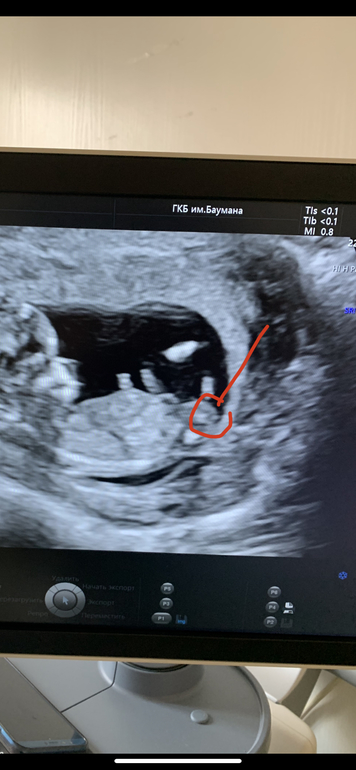

Девочки, привет!) сегодня была на первом скрининге, от эмоций забыла спросить узистку видно ли уже пол. Но сделала фотки. Начала вглядываться и кажется нашла какую-то пипирку. Опытные девушки, Как думаете это он или она, или вообще не видно и это что-то другое?

Срок 13 недель и 1 день.

На этом этапе развития пипирка торчащая есть и у мальчиков и у девочек ... поэтому смотрят по наклону полового бугорка... у вас на мой взгляд очевидно девочка 🌺